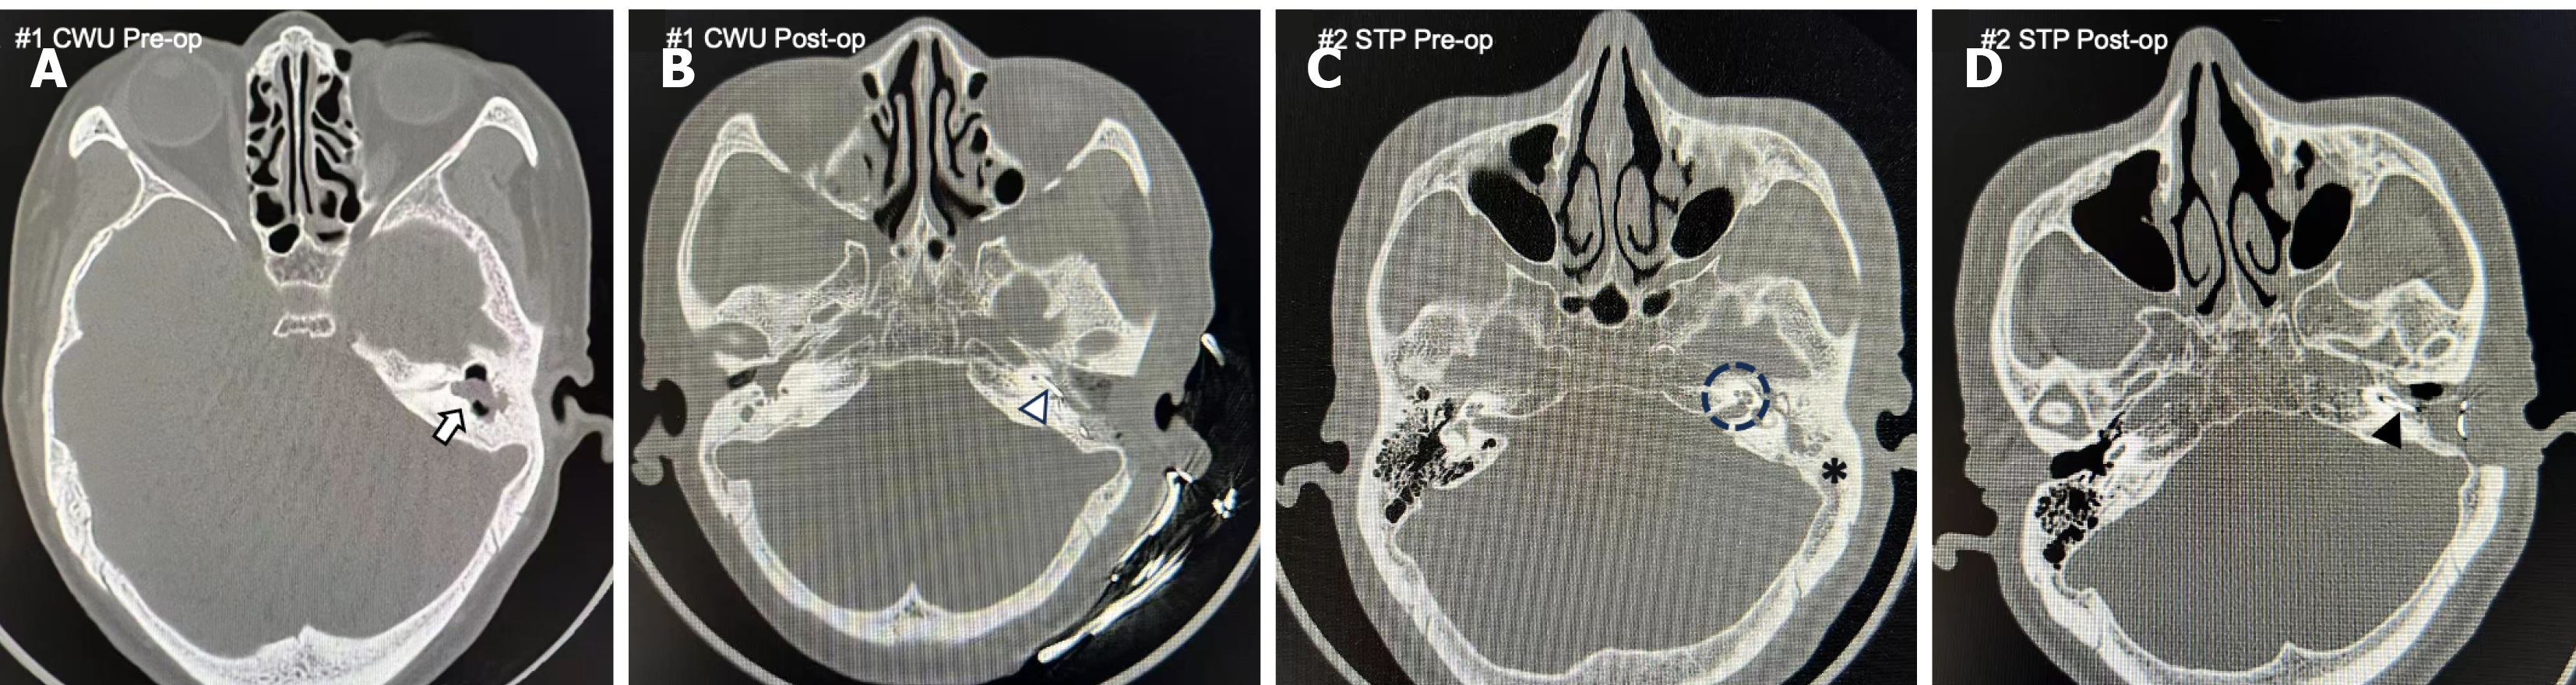

The predictive power of HRCT is best illustrated by comparing two distinct clinical scenarios.

Case 1: A 71-year-old male with cholesteatoma presented with classic, localized disease on preoperative HRCT (Figure 2A and B). The scan showed soft tissue pathology confined to the epitympanic space, with a well-aerated mastoid and intact posterior canal wall. The clear radiological evidence allowed for a conservative CWU mastoidectomy to safely remove the disease while preserving the natural ear canal anatomy. Surgery proceeded as planned, confirming localized cholesteatoma and allowing successful simultaneous cochlear implantation.

Case 2: By contrast, a 60-year-old female presented with a more complex radiological profile (Figure 2C and D). HRCT revealed widespread opacification throughout the middle ear and entire mastoid cavity. Critically, the scan revealed severe (grade III) CO, posing a significant challenge for electrode insertion and requiring specialized techniques. Imaging unequivocally indicated that a limited, conservative approach would be insufficient and unsafe. Consequently, a radical STP was scheduled to ensure complete disease removal. Preoperative awareness of severe CO allowed for patient counseling regarding the high probability of only partial electrode insertion. The extent of the disease and CO was confirmed during surgery, validating the radical surgical approach taken.

These cases illustrate our central finding: Complete opacification of the mastoid cavity was the most reliable predictor for the necessity of a radical procedure (CWD/STP), which was present in all 5 cases where such a procedure was needed. Conversely, when the disease was confined to the middle ear spaces with a clear mastoid, the CWU approach was successful in all 7 applicable cases. Postoperative computed tomography confirmed satisfactory electrode placement in all 12 patients. The baseline demographic characteristics were comparable between the CWU and CWD/STP groups (all P > 0.05; Table 1). Of note, Table 1 includes key preoperative and postoperative auditory outcomes (speech discrimination scores) for both groups where available, enhancing the clinical relevance of our study’s findings.